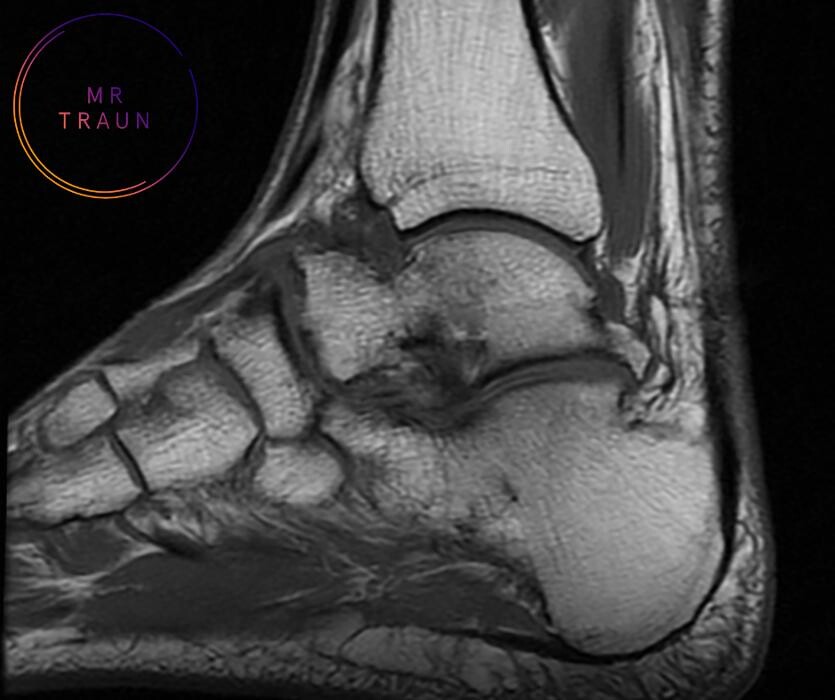

Wir bieten Ihnen die präzisesten Methoden der bildgebenden Diagnostik im Bereich der Magnetresonanztomografie. Bildgebende Diagnostik. Ohne Wartezeit. Private Magnetresonanztomografie in Traun.